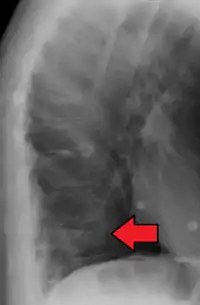

Compression fracture of the fourth lumbar vertebra post falling from a height.

A compression fracture is a collapse of a vertebra. It may be due to trauma or due to a weakening of the vertebra (compare with burst fracture). This weakening is seen in patients with osteoporosis or osteogenesis imperfecta, lytic lesions from metastatic or primary tumors,[1] or infection.[2] In healthy patients, it is most often seen in individuals suffering extreme vertical shocks, such as ejecting from an ejection seat. Seen in lateral views in plain x-ray films, compression fractures of the spine characteristically appear as wedge deformities, with greater loss of height anteriorly than posteriorly and intact pedicles in the anteroposterior view.[3]

Compression fractures are usually diagnosed on spinal radiographs, where a wedge-shaped vertebra may be visible or there may be loss of height of the vertebra. In addition, bone density measurement may be performed to evaluate for osteoporosis. When a tumor is suspected as the underlying cause, or the fracture was caused by severe trauma, CT or MRI scans may be performed.